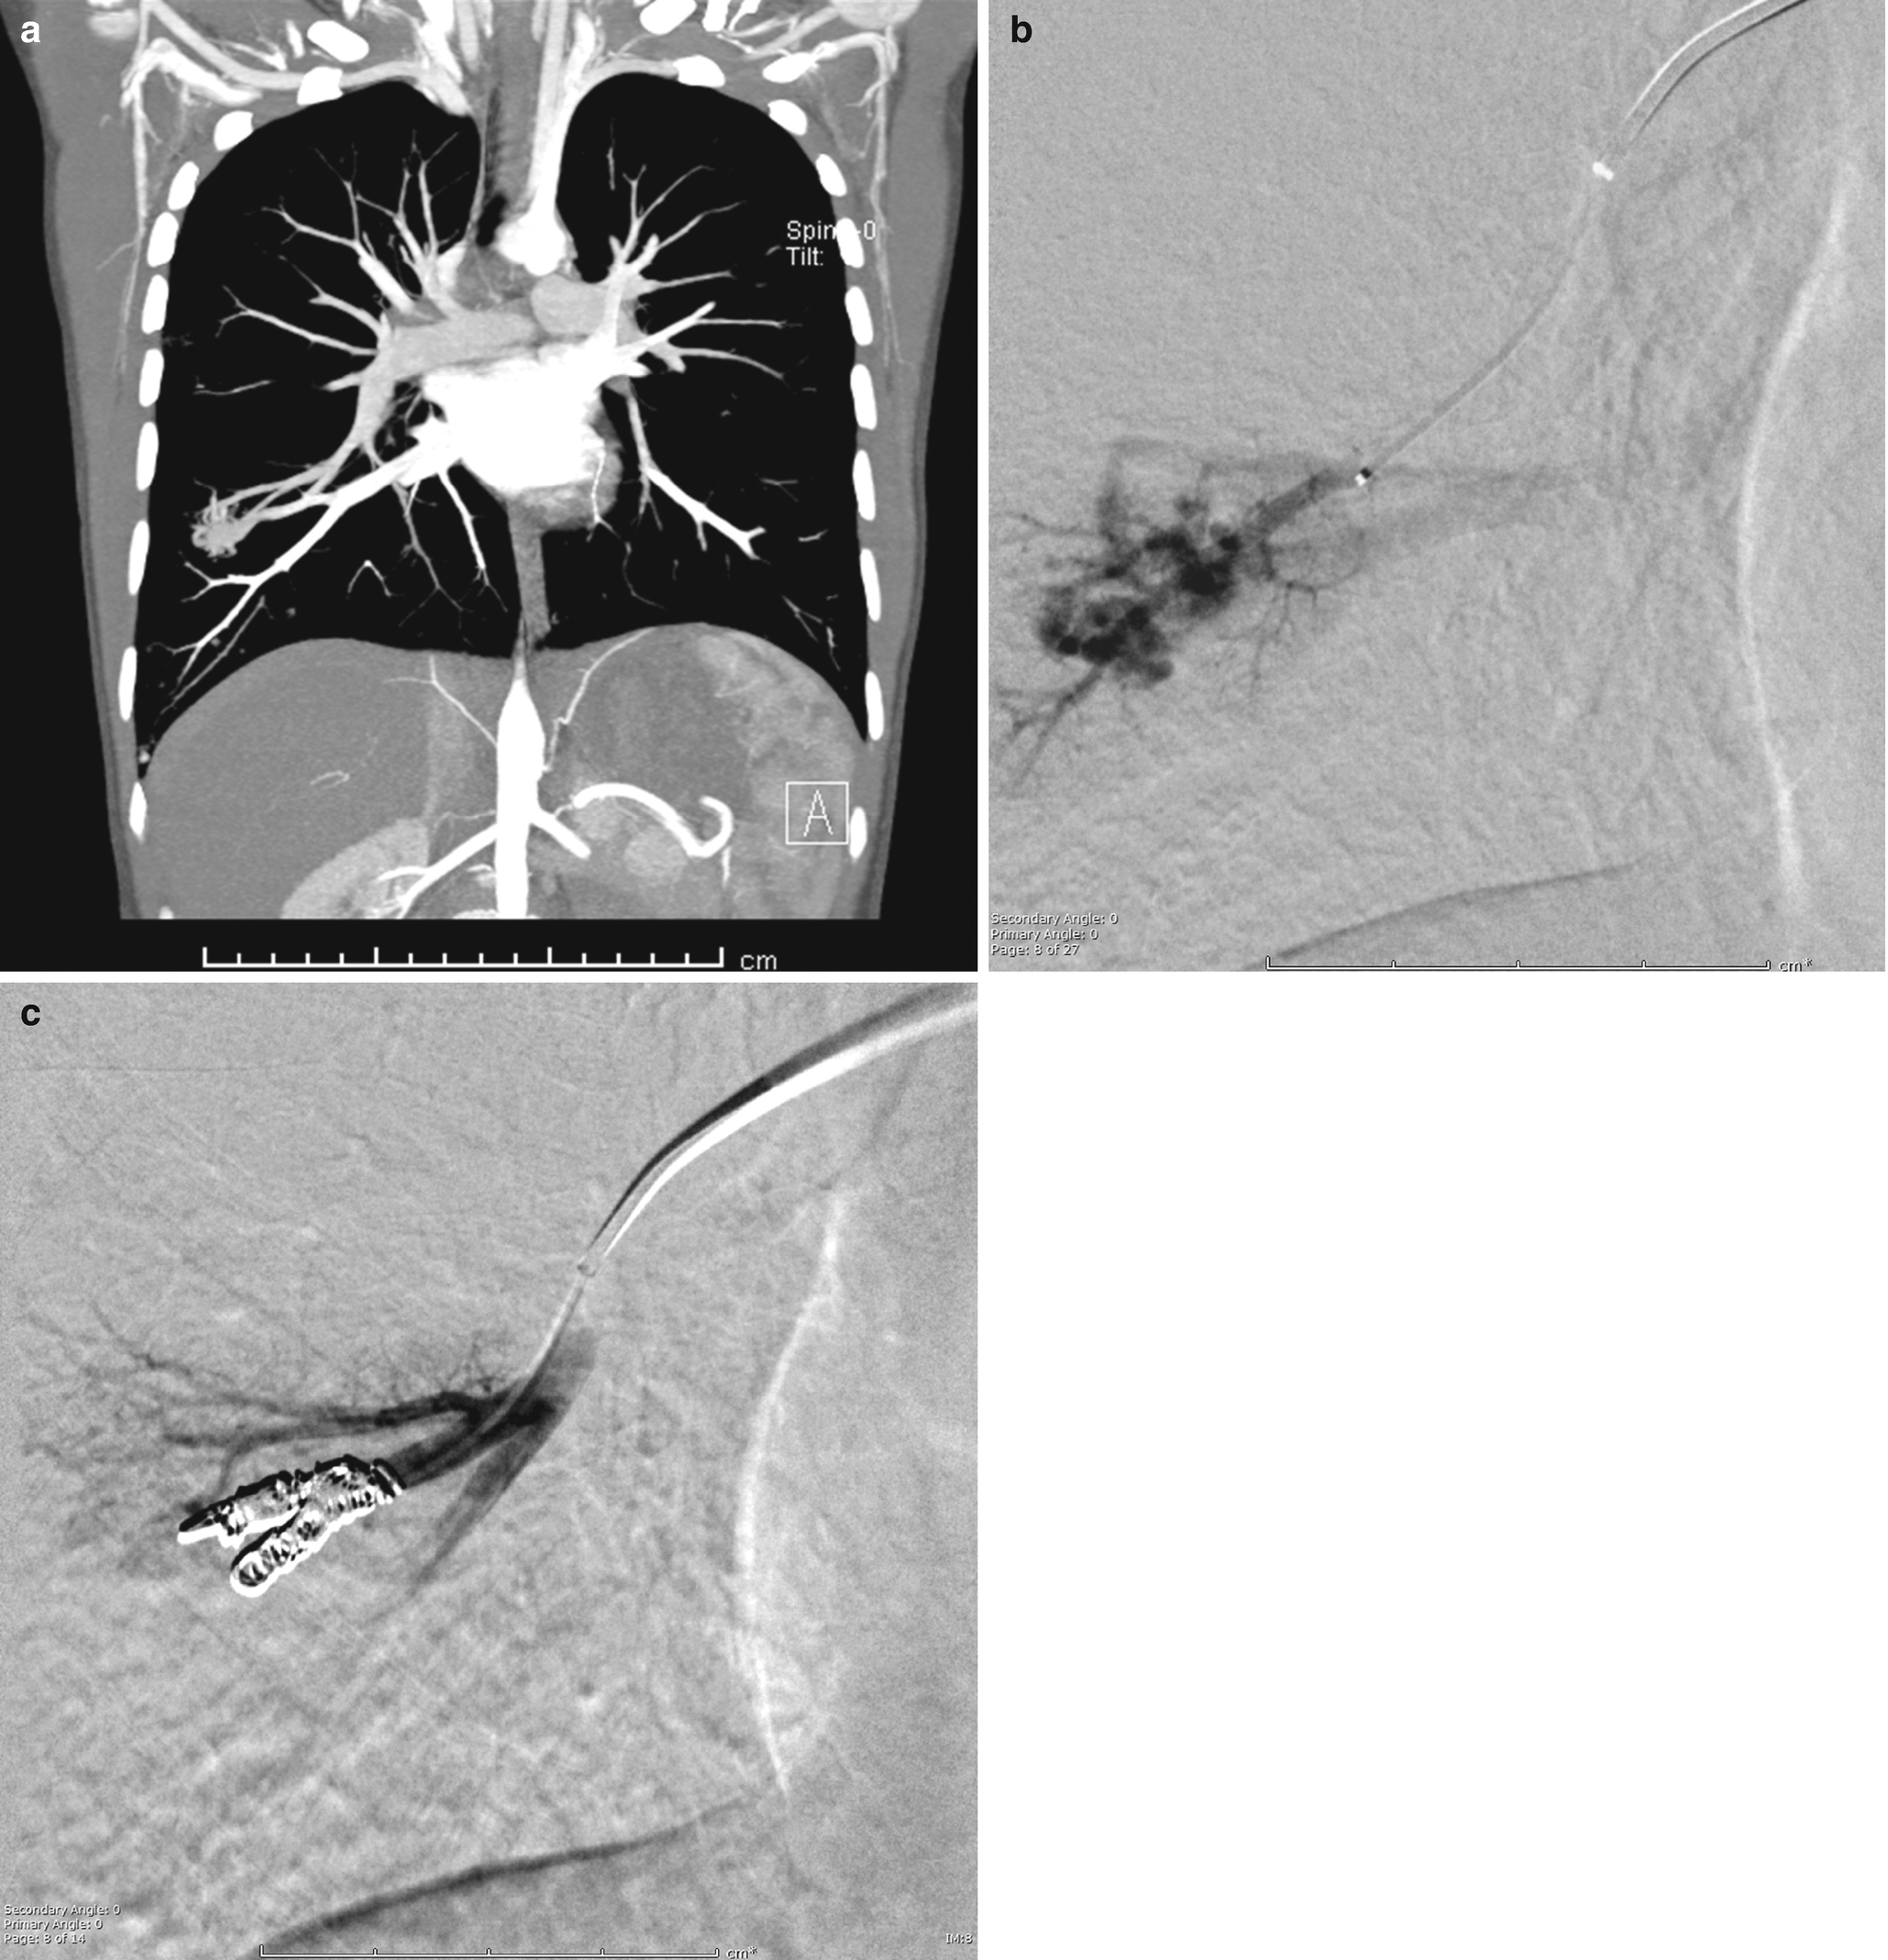

Pediatric Percutaneous Chest Intervention Springerlink